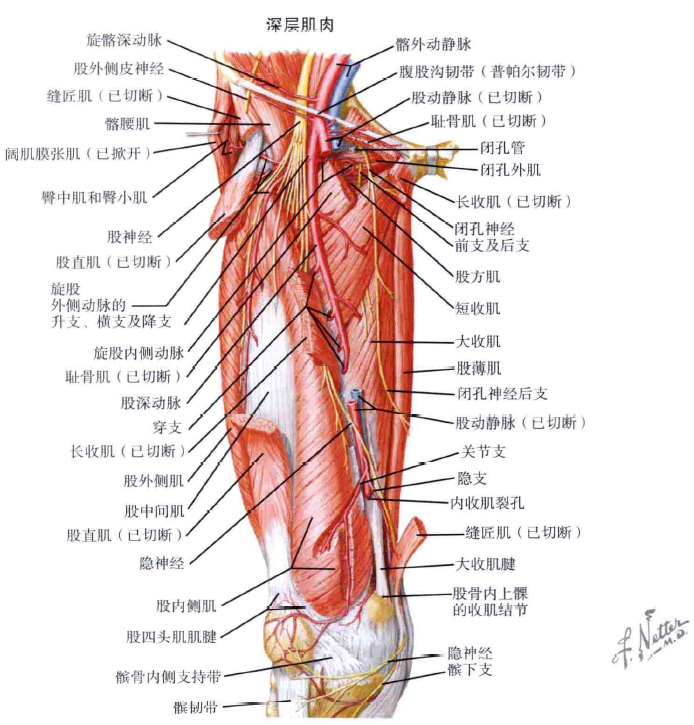

其次,大家可以看看髋关节周围重要的肌群、血管神经:

右侧髋关节-前方-深层重要肌群及血管神经

右侧髋关节-后方-重要肌群及血管神经